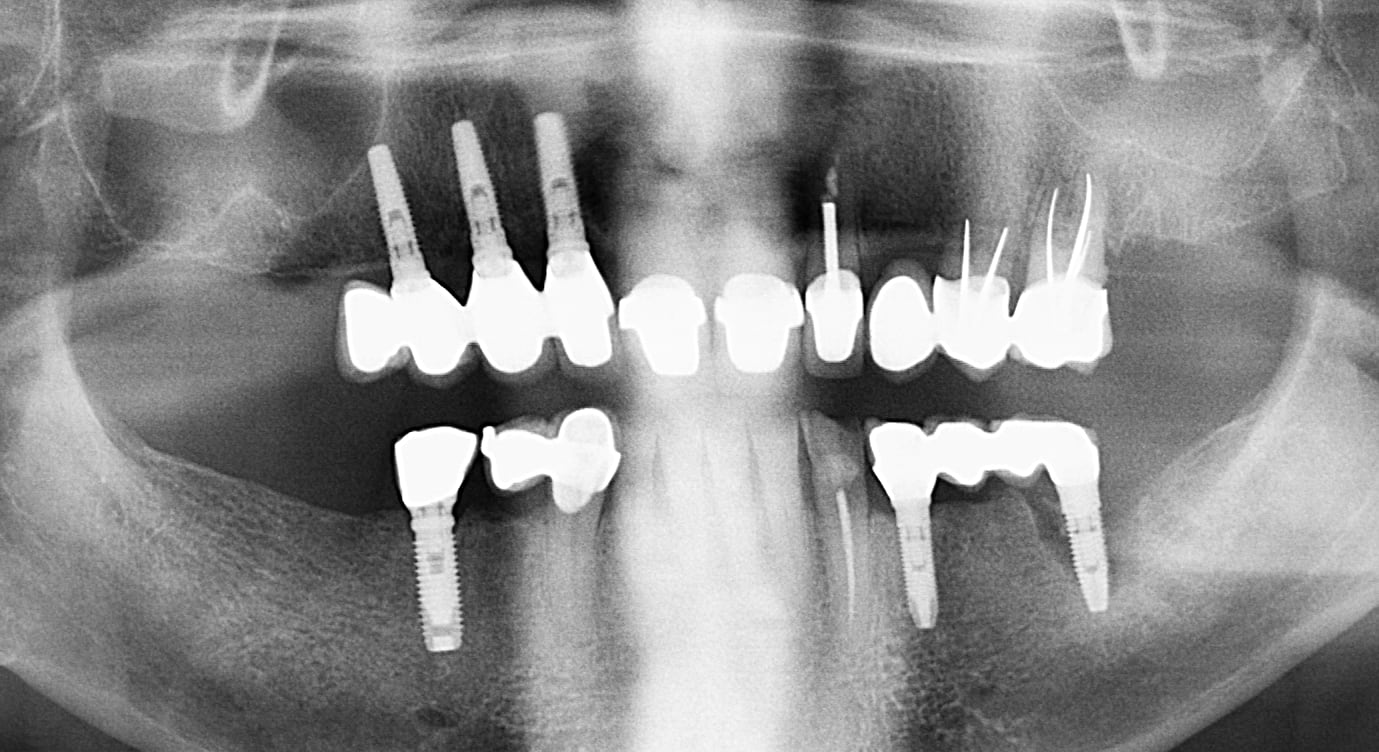

Patient d'une petite soixantaine d'années. Brossage correct et brossettes. Pas de prothèse inférieure.

Il y a un "contrat" sur la 26, pas sur les voisines. Et il ne fallait pas mettre d'implant pcq la zone 11-21 est électriquement anormale. Perdu d'avance.

"L’os me paraît bien dense à la mandibule au passage. Faut chercher de ce coté"

86 ans.

Implants posés il y'a une quinzaine d'années.

Tu commences à me connaître, un rien m’amuse . En tout cas , expliquer que l’implant antérieur est compromis à cause d’une raison électrique plutôt qu’une raison de manque de calage postérieur oui effectivement ça me fait sourire. Vous prenez une chaise avec 4 pieds qui la soutiennent . Et vous enlevez les deux pieds postérieurs. Qu’est ce Qu’il se passe ? Ça se casse la gueule. Là c’est pareil pas de calage postérieur => les dents antérieures morflent y compris l’implant .

Pourquoi à ton avis il y a plus de perte d’os sur l’implant au niveau de l’incisive ? C’est tout à fait normal qu’on constate une telle perte osseuse . Trois facteurs sont en cause ici : l’occlusion (pas de calage) la parodontite , plus la pose de l’implant (son orientation) . D’autant plus que l’incisive centrale est d’avantage utilisée qu’une incisive latérale. Surtout qu’on le sait tous : si il y a eu pose d’implant ça veut dire qu’il y a eu extraction. Qui dit extraction dit perte d’os . Donc déjà dans cette zone on avait moins d’os en verticale et en épaisseur . Sauf si le dentiste a reconstruit une épaisseur osseuse ou fait une expansion, ce que je doute fortement. Donc déjà faut partir du principe que l’implant ait été posé dans un os moins épais que ce qu’on trouve au niveau de ses latérales par exemple.

Et sans parler de l’orientation de l’implant ! Est-ce qu’il a été posé dans l’axe de la centrale ? J’en ai pas l’impression . Faut pas s’ étonner si on a plus d’os perdu sur un implant posé obliquement et dont l’axe a été rattrapé par le pilier et la couronne. Déjà on sait que le mec n’a pas posé ça correctement dans le sens horizontal. Alors je n’ose pas imaginer dans le sens sagittal comment ça a été posé :) .